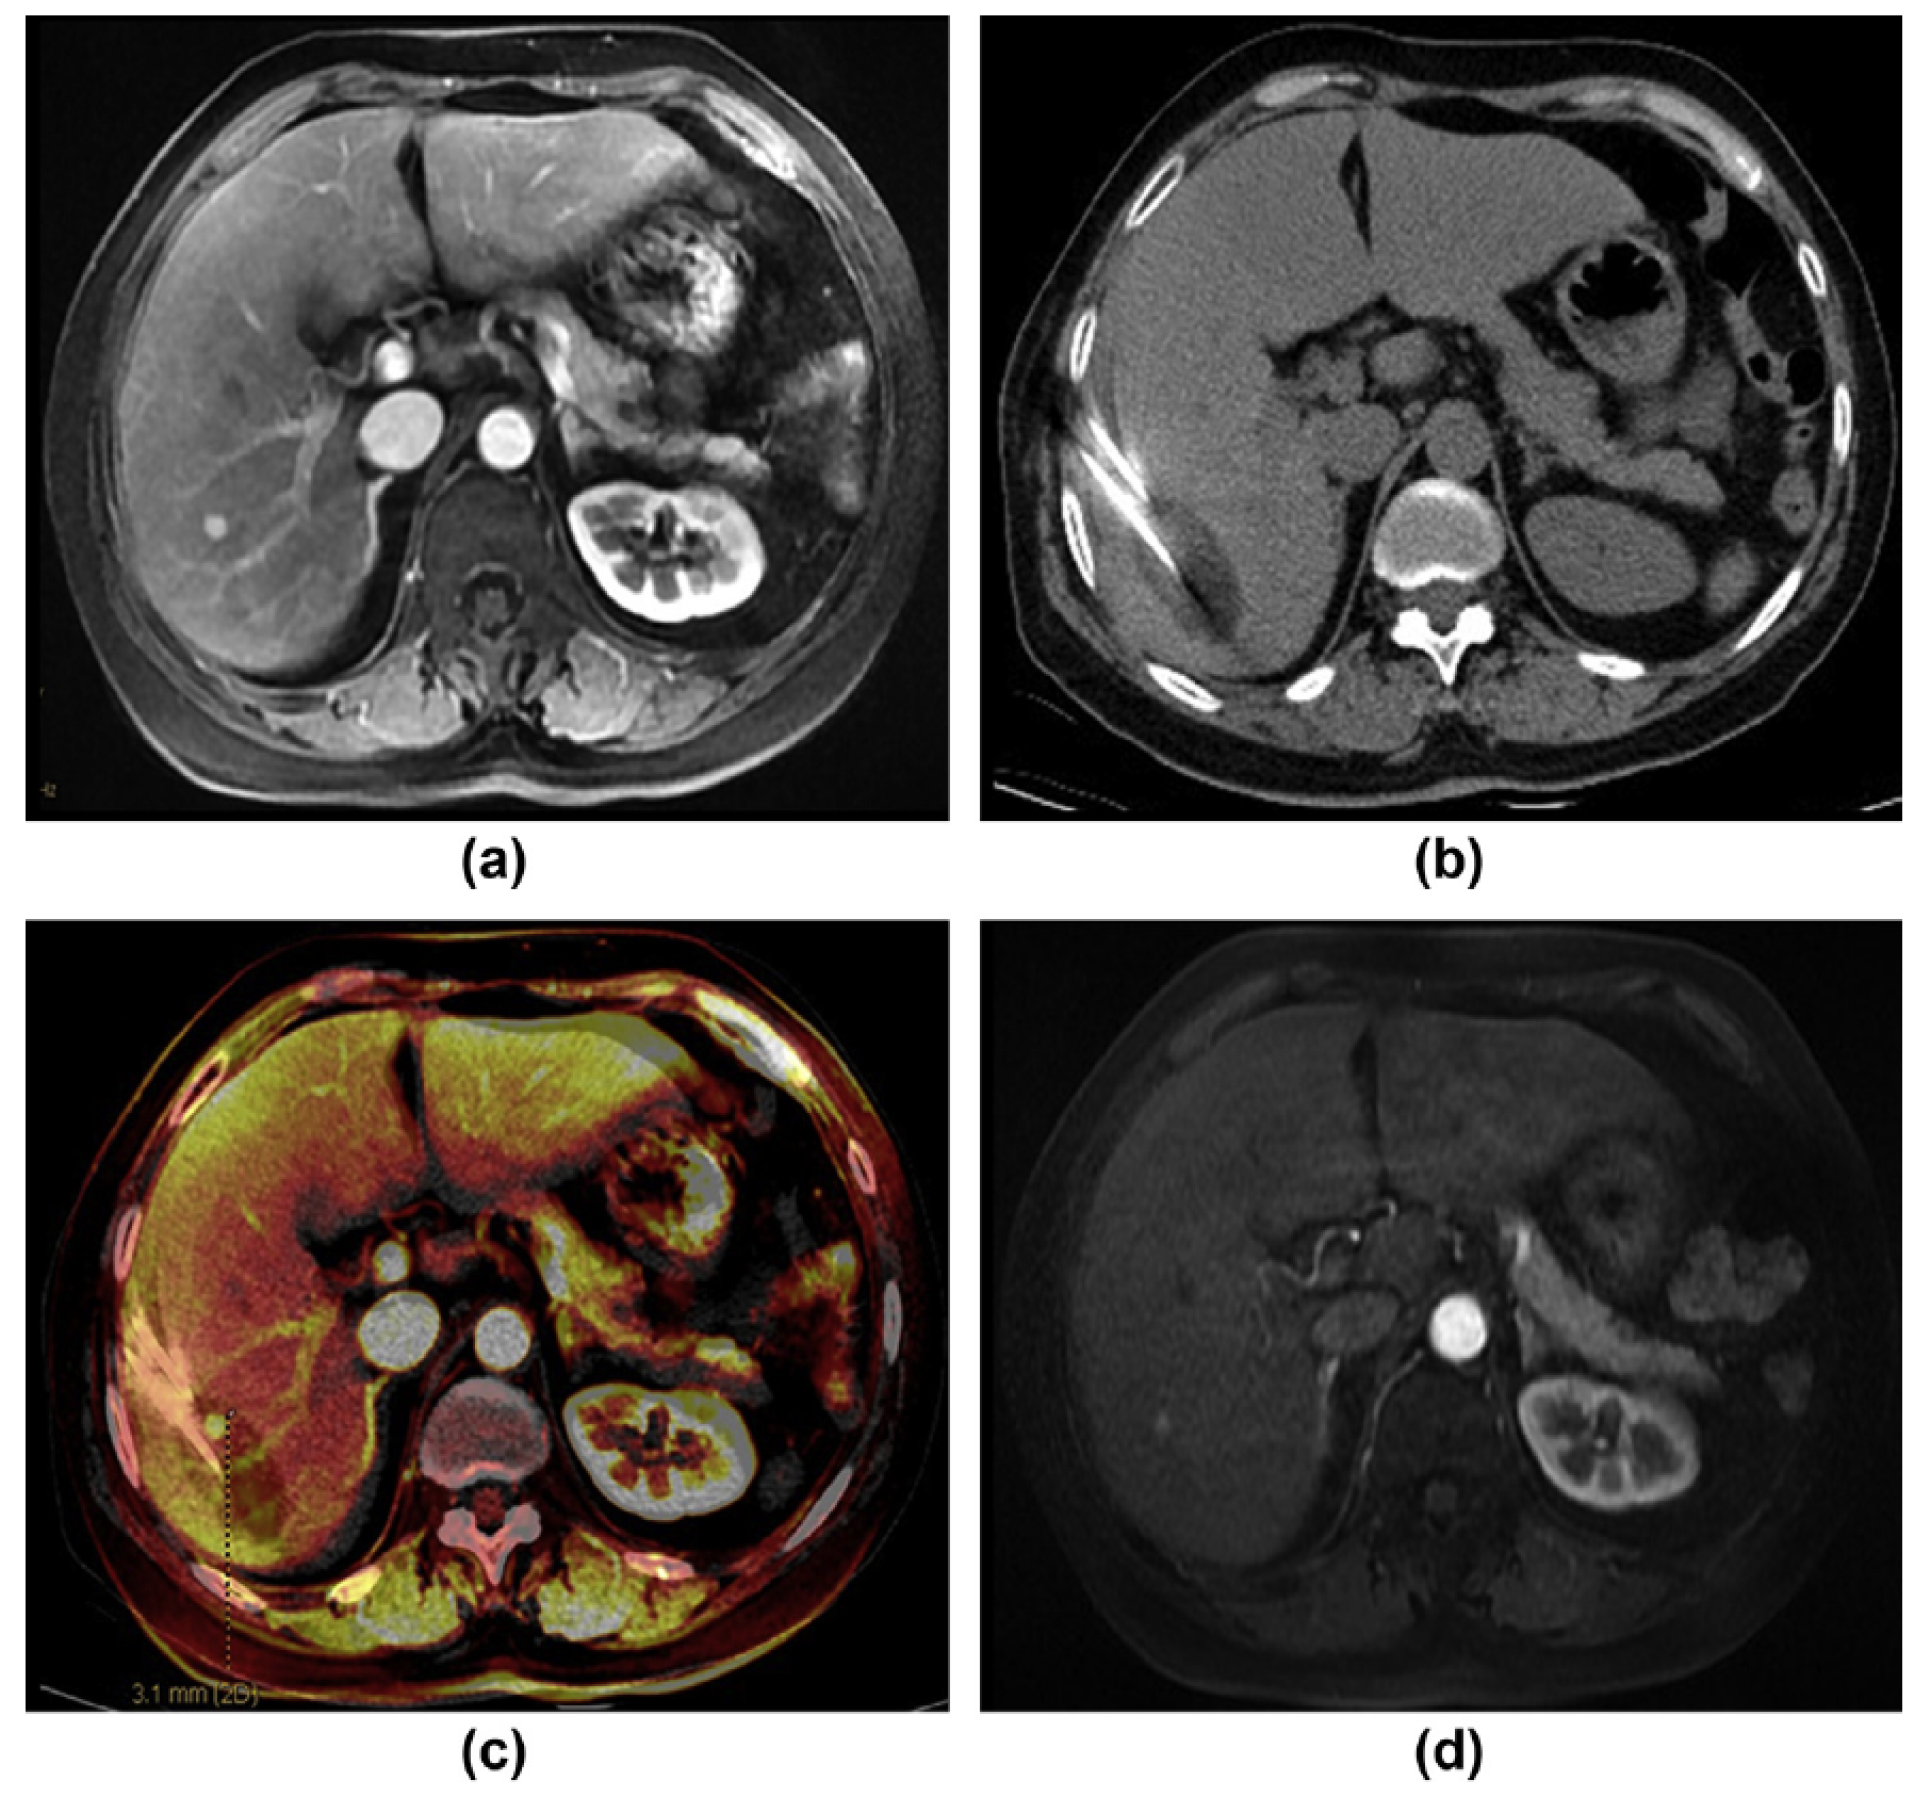

5.1. Ultrasonography/MRI, Ultrasonography/CT and Ultrasonography /PET-CT

5.1.1. Utility of CEUS/MRI in Diagnosis and Treatment of Small Liver Cancer

5.1.2. Utility of CEUS/MRI in Radiofrequency Ablation of Liver Cancer

5.1.3. Utility of CEUS/PET-CT in Transarterial Chemoembolization Treatment of Liver Cancer

5.2. CT/MRI

5.3. PET/CT & PET/MRI